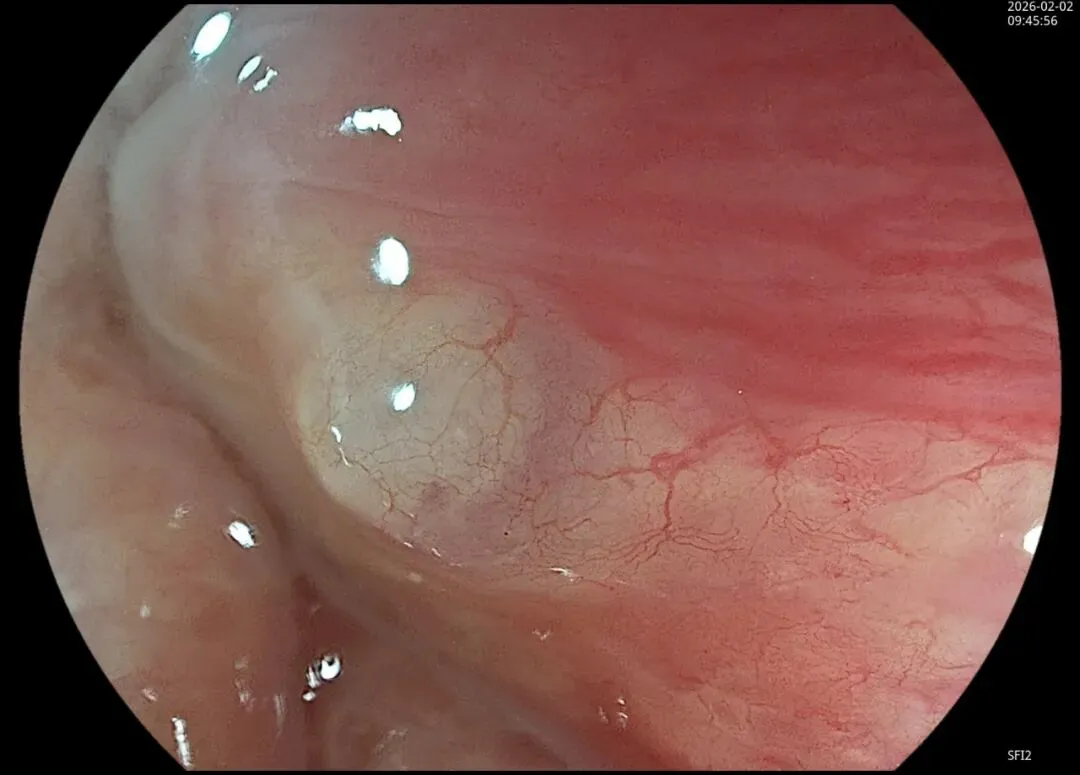

这一期不用码字,挺好的,很可惜一直没机会听过胡导讲的关于这个“花环征”的大课,学习内容来源于雨夜大师的号花环征:AIG背景的胃食管结合部的黄色颗粒状隆起及半透明“泡状”改变

补充自己在两例A型胃炎/AIG 观察到的“花环征”,巩固下学习效果。。。

1.白光表现为胃食管交界处黄色颗粒状隆起及半透明“泡状”改变